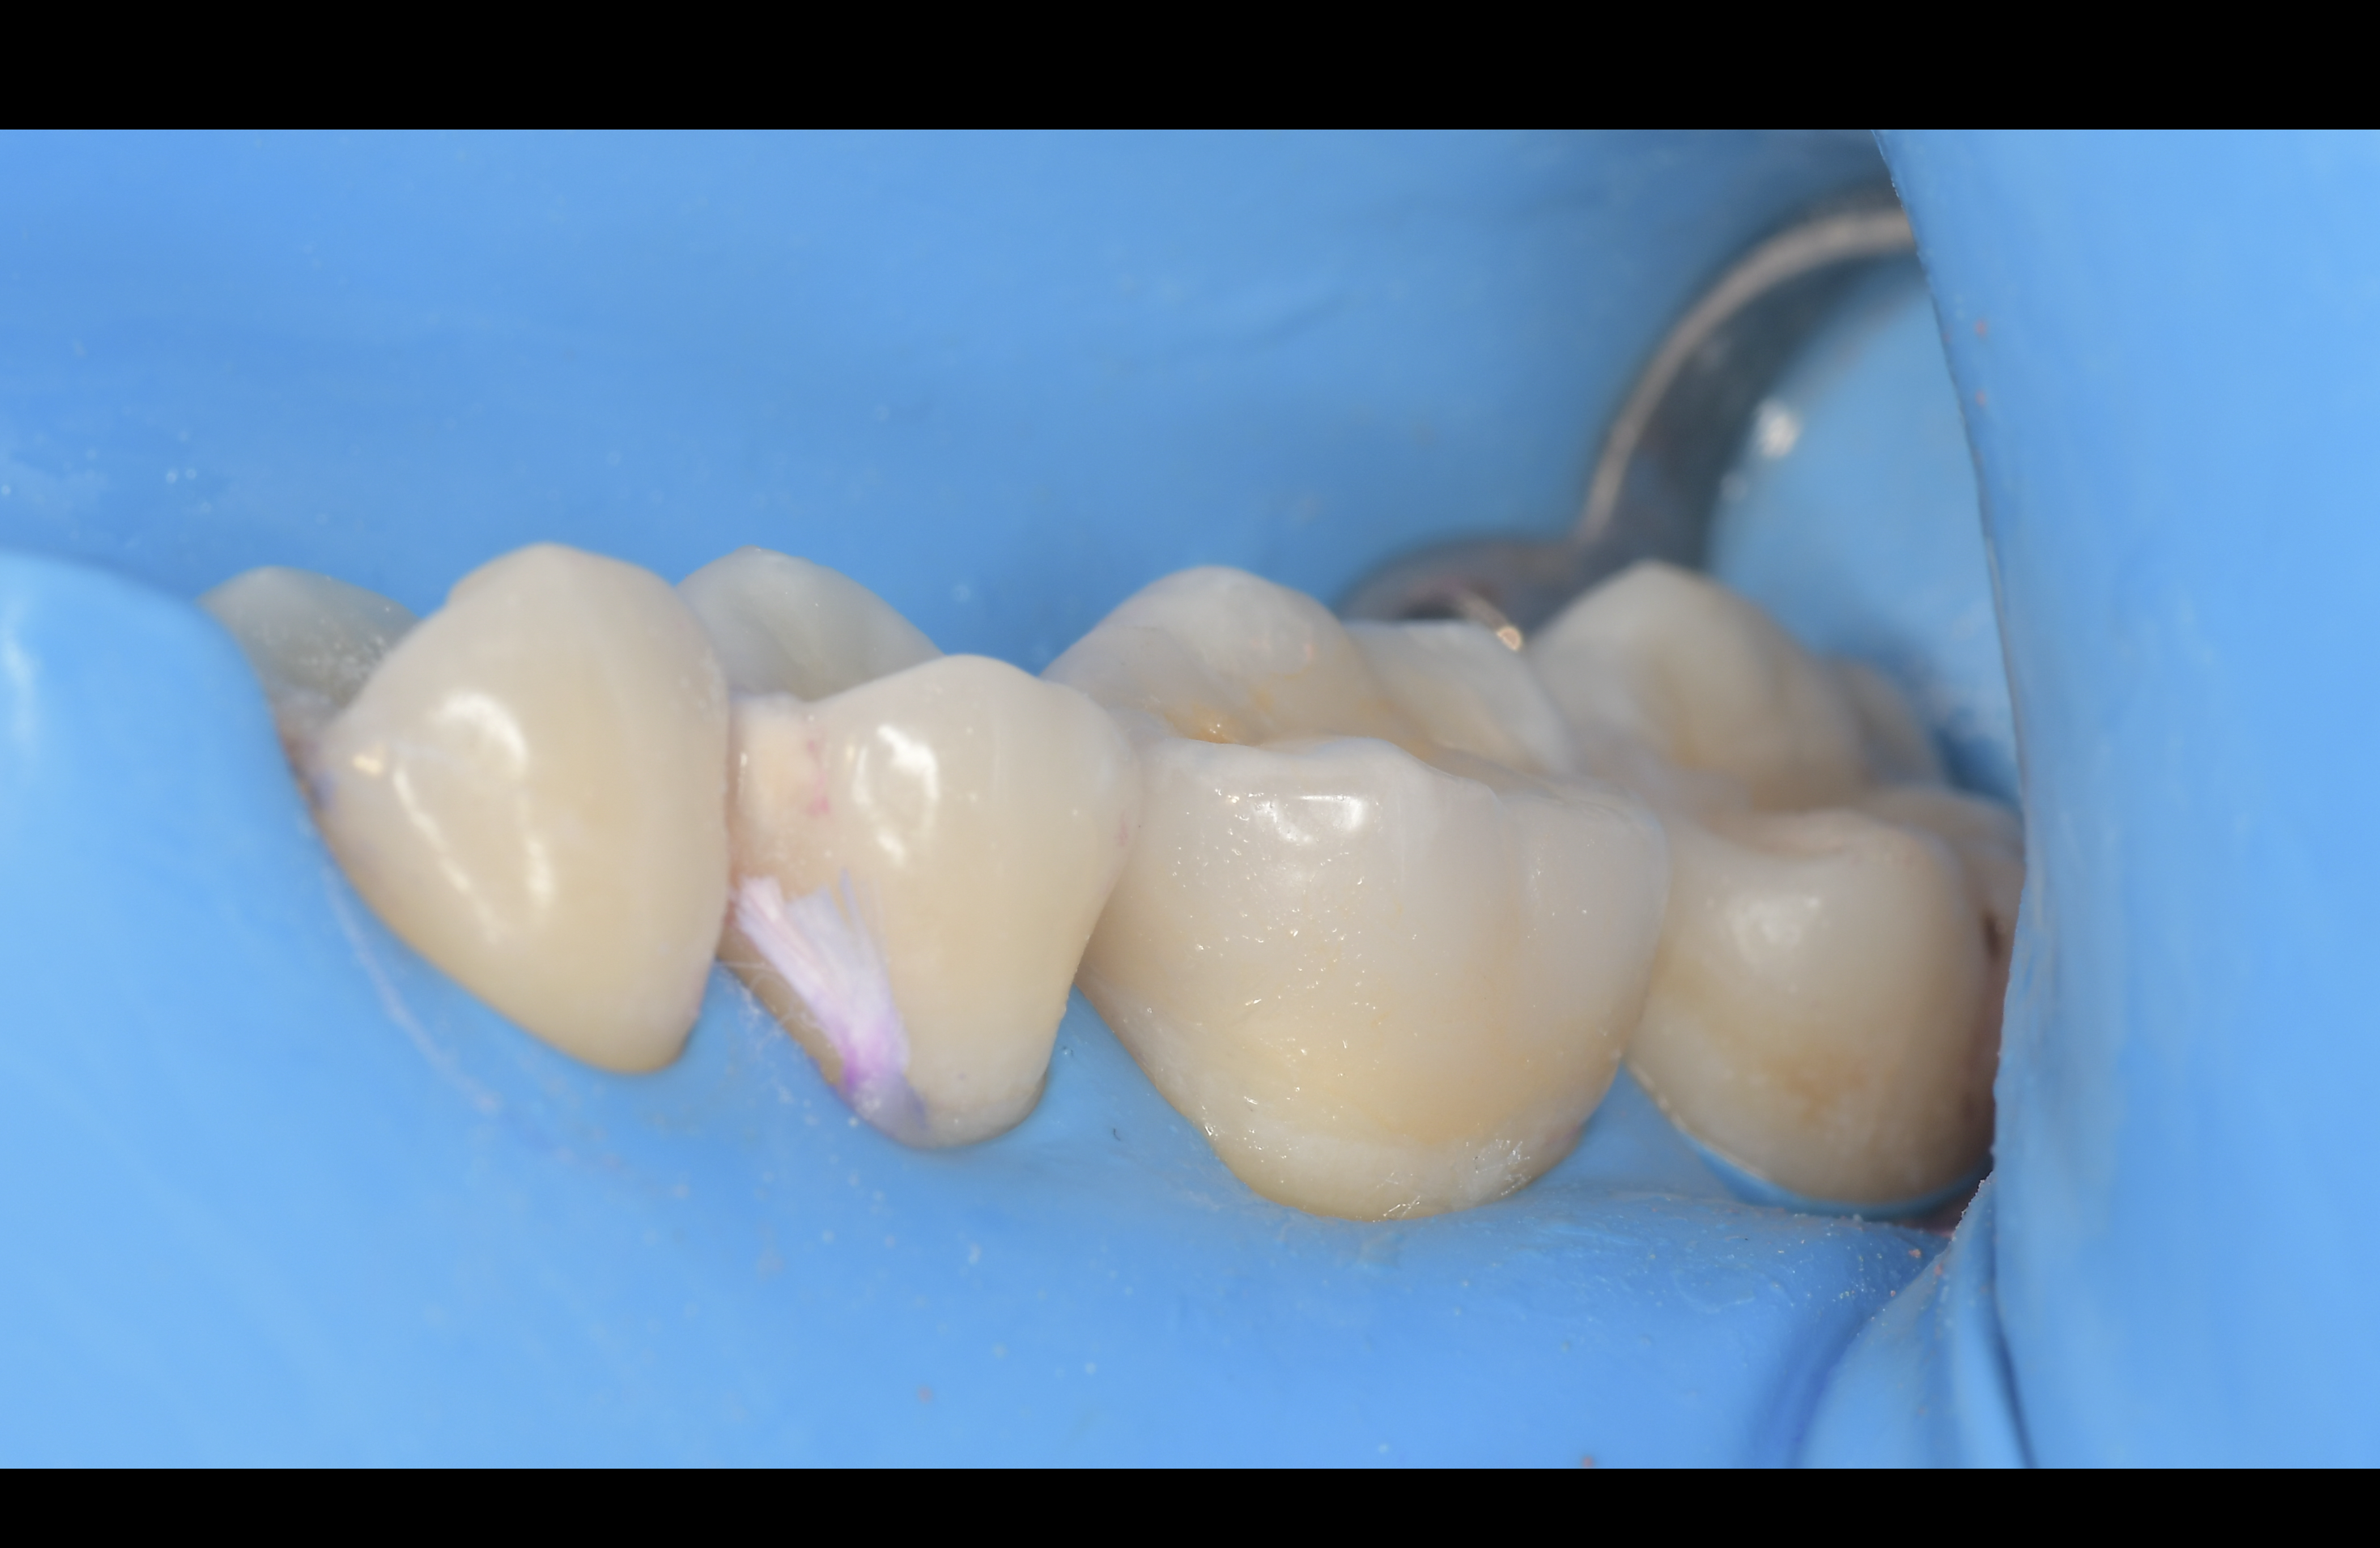

ラバーダムシートの装着、歯面の清掃・表面処理、セラミックの前処理、接着剤の塗布、硬化、マイクロスコープによるセメント除去といった一連の工程を科学的根拠に基づいて丁寧に管理しています。

接着を成功させるために欠かせないのが、ラバーダム防湿です。

ラバーダムとは、治療する歯のまわりを薄いゴムのシートで覆い、唾液中の細菌による汚染や湿気を完全に遮断する処置のこと。

この防湿を行うことで、歯の表面が常に乾燥した清潔な状態に保たれ、接着剤が最大限の性能を発揮します。